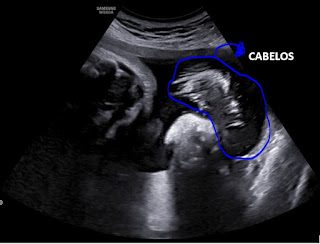

- 1ª, Baby Boy está lindo e formoso, mas ainda não quer mostrar a carinha...ainda bem que dessa vez perguntamos antes pra médica se ia dar pra ver alguma coisa no 4D antes de pagar...

Ele tá com 2.598 kg e medindo 46 cm e é super cabeludooo...kkkk!